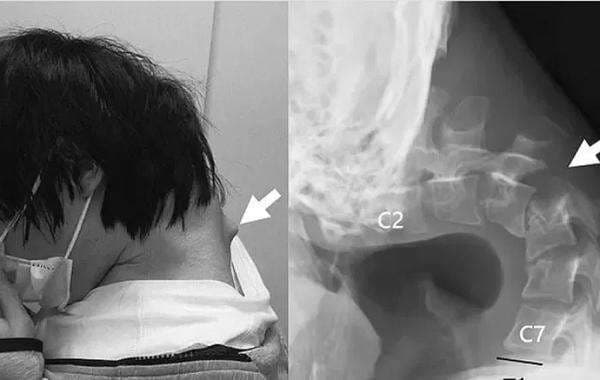

Pria asal Jepang itu diduga menghabiskan sebagian besar waktunya bermain ponsel. Akibat terlalu lama menunduk, timbul benjolan besar di bagian belakang lehernya sehingga ia tidak dapat lagi mengangkat kepalanya sendiri menggunakan otot-otot lehernya.

Pemuda ini kemudian menghabiskan sebagian besar harinya terkunci di kamarnya sendirian, bermain ponsel. Menghabiskan waktu berjam-jam dengan leher tertekuk untuk melihat ponselnya menyebabkan tonjolan besar terbentuk di bagian belakang lehernya.

Hasil pemindaian menunjukkan bahwa tulang belakang lehernya terdistorsi dan terkilir, dan jaringan parut telah terbentuk di tulang belakang bagian atasnya akibat terlalu meregang selama jangka waktu lama.